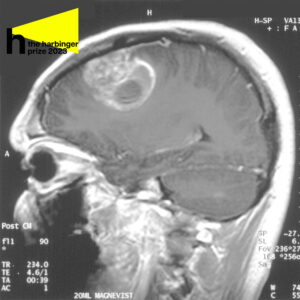

Sagittal MRI with contrast of a glioblastoma in a 15-year-old boy

Glioblastoma is notorious because of its thin branches that spread through the healthy brain tissue and makes the tumor extremely difficult to remove – a part of the tumor visible to the naked eye is only a small fraction of the entire glioblastoma. What grows underneath the healthy tissue is often the most malignant and unpredictable, because neural pathways aid the tumor in spreading to opposite sides of the brain.

While removing a tumor, surgeons often cut out healthy tissue surrounding it (called the margin) to be sure they eliminate as many damaging cells as possible. Glioblastoma often originates in the frontal and temporal lobes of the brain, critical for processing memory, emotions, auditory information, as well as sensory input. Neurosurgeons have to navigate meticulously to limit the damage to the brain.